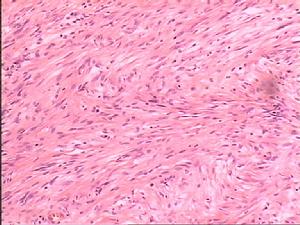

喉鏡檢查可見淡紅色或暗紅色、表面不平、呈乳頭狀的腫瘤,幼兒患者的基底甚廣,成人者以單個帶蒂較多,常發生於聲帶、室帶及聲門下區。亦可蔓延及咽或氣管。

診斷依據

1.聲嘶、乾咳、喉鳴、呼吸困難。 2.喉鏡檢查:聲帶、假聲帶前聯合等處單發或多發蒼白、或灰紅色、表面粗糙不平呈乳頭狀腫物。重者達聲門下及氣管。 3.病理活檢或摘除腫物後送檢。